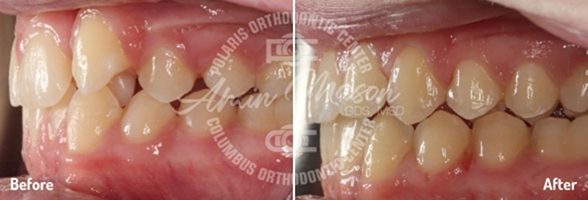

Case 1

Following teenage female patient visited our office with the chief complaint of “crooked teeth.” The patient expressed not being happy with her smile and was not eager to smile. They presented with mild class 2 occlusion, crowding of arches, and crossbite of maxillary lateral incisor teeth. The patient did not wish to have braces and requested clear aligners. She was treated with Invisalign clear aligners and elastics. Total treatment time was 26 months. Patient achieved excellent results.